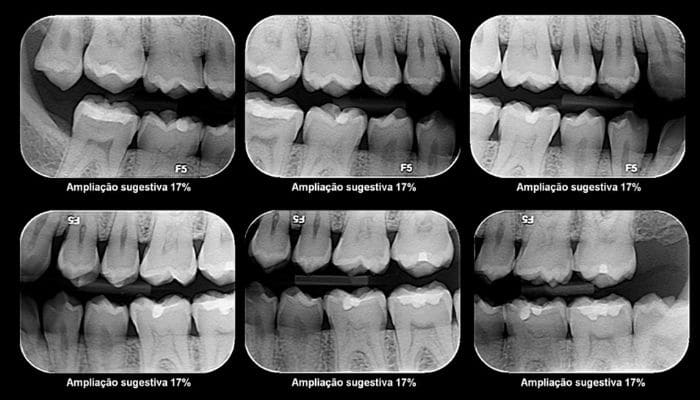

1 – Extração do siso -retirada dos terceiros molares, popularmente conhecidos como dentes do juízo ou dentes do siso.